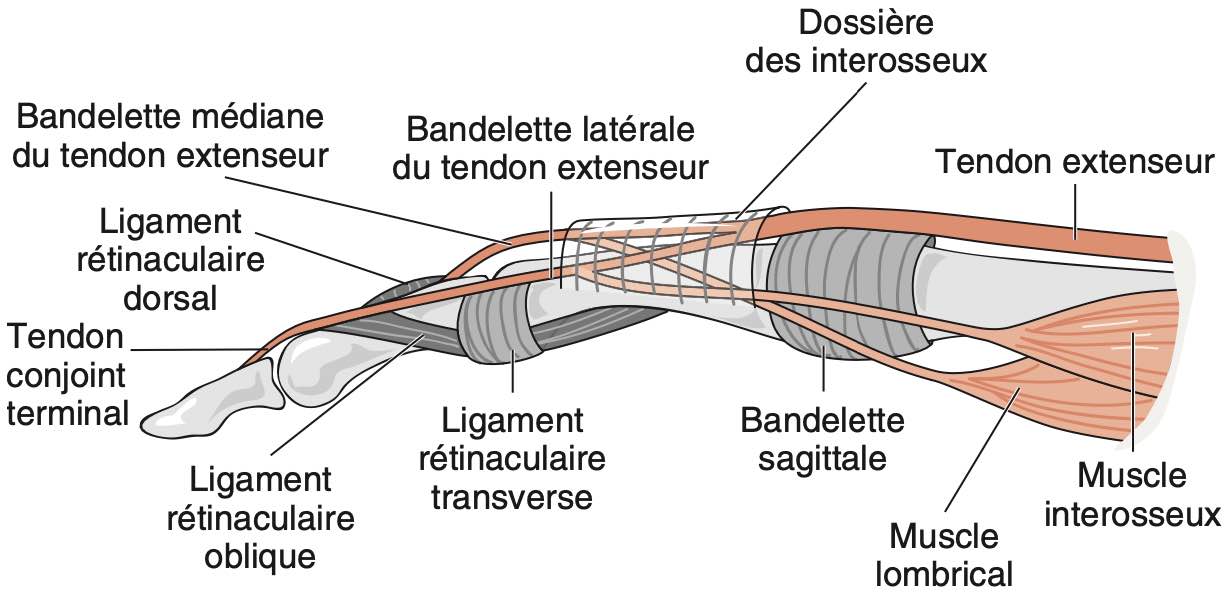

Rupture bandelette sagittale radiale 3ème rayon

Infiltration péritendineuse avec hyperhémie Doppler en regard de l'articulation métacarpo-phalangienne du 3ème rayon.

Subluxation ulnaire du tendon extenseur. Pas d'anomalie de son échostructure.

Respect des bandelettes sagittales des autres MCP.